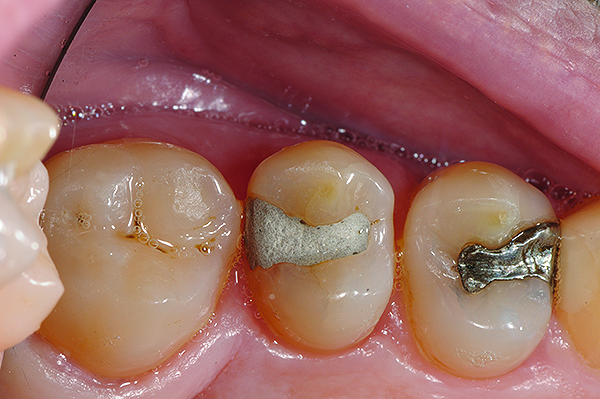

Fig 8. Cavities were bulk-filled with high-viscosity auto-curing GIC.

Figure 8

Fig 9 and Fig 10. After GIC was manually condensed and shaped, a nanofilled resin glaze was liberally applied to the surface of the finished restoration (Fig 9) and light-cured (Fig 10).

Figure 9

Figure 10

Fig 11. Completed bulk-filled GIC restorations showing excellent esthetics and surface smoothness.

Figure 11